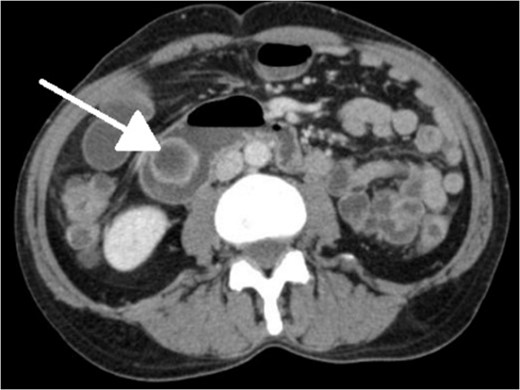

With regard to diagnostic workup, the literature has described cases with similar results to ours. Small bowel contrast studies frequently show smooth-walled polypoid filling defects within the duodenal bulb, and CT imaging is useful for delineation of adjacent structures including the common duct and pancreas [1]. Moreover, similar to the pathological results found in our patient, upper endoscopy biopsies are often equivocal as they are submucosal-based lesions [1]. The most useful diagnostic study, however, is endoscopic ultrasound, which may help distinguish the consistency and bowel layer of origin [2, 6], which unfortunately was not available at our institution.